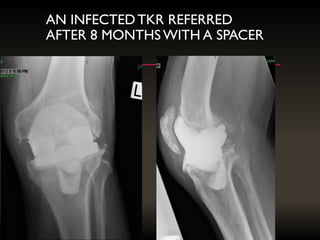

AN INFECTEDTKR REFERRED

AFTER 8 MONTHS WITH A SPACER

REVISION: 9/6/2016, CURRENT OFF THE SHELF

LCS AND AUGMENT OF IMPLANT, NOT BONE STOCK

Inventory required 3thicknesses of hemi- augments X 6 trays = 18 , or full size augments = 18: Grand total could be 36 parts REVISION: 9/6/2016, CURRENT OFF THE SHELF LCS AND AUGMENT OF IMPLANT, NOT BONE STOCK

AN INFECTEDTKR REFERRED AFTER8 MONTHS WITH A SPACER